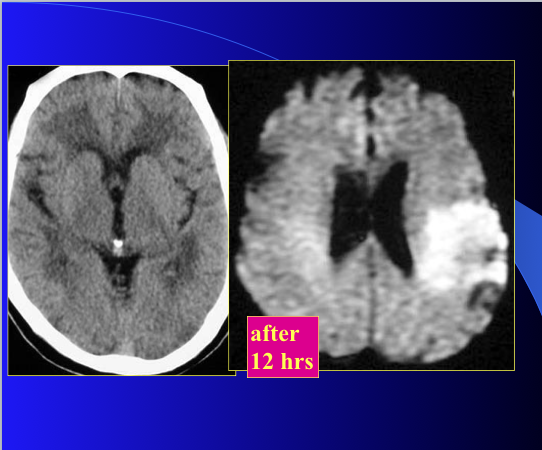

what type of image?

what is the pathology?

what enhancement is used?

CT

stroke

DWI